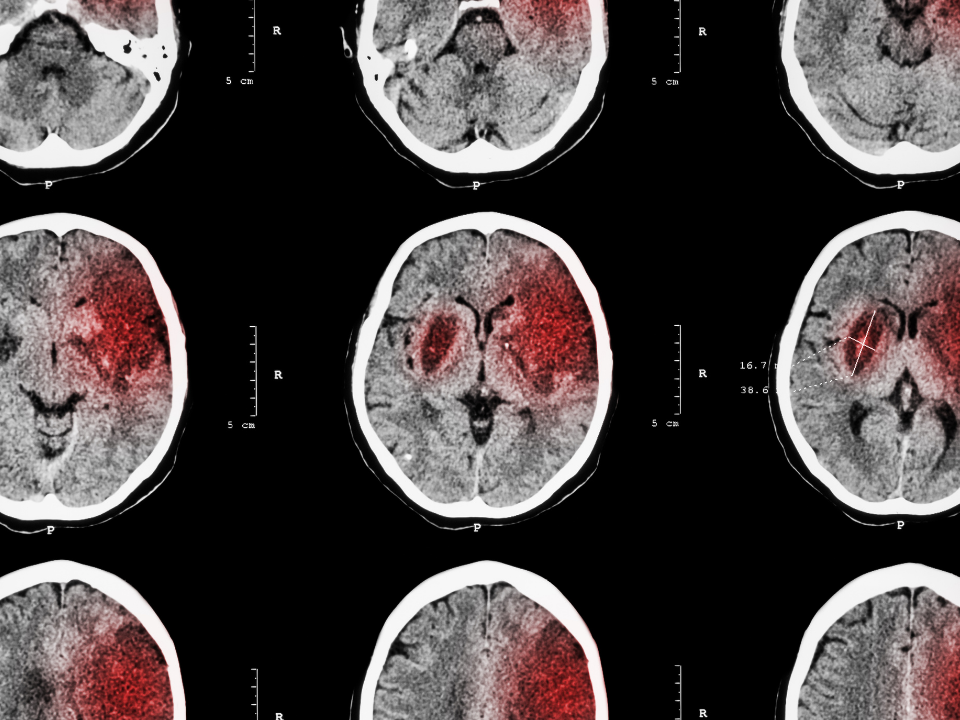

Esse é o caso de um software, desenvolvido pela empresa israelense Aidoc, que é capaz de identificar com mais precisão derrames do tipo hemorrágico -quando uma artéria se rompe, causando sangramento no cérebro.

O programa usa um algoritmo para analisar o resultado de tomografias e destaca áreas com sangramento que podem passar despercebidas pelo olho humano.

A tecnologia também permite detectar outros tipos de doenças, como tumores cerebrais. “É um algoritmo especialista em sangramentos no crânio”, explica Santos.